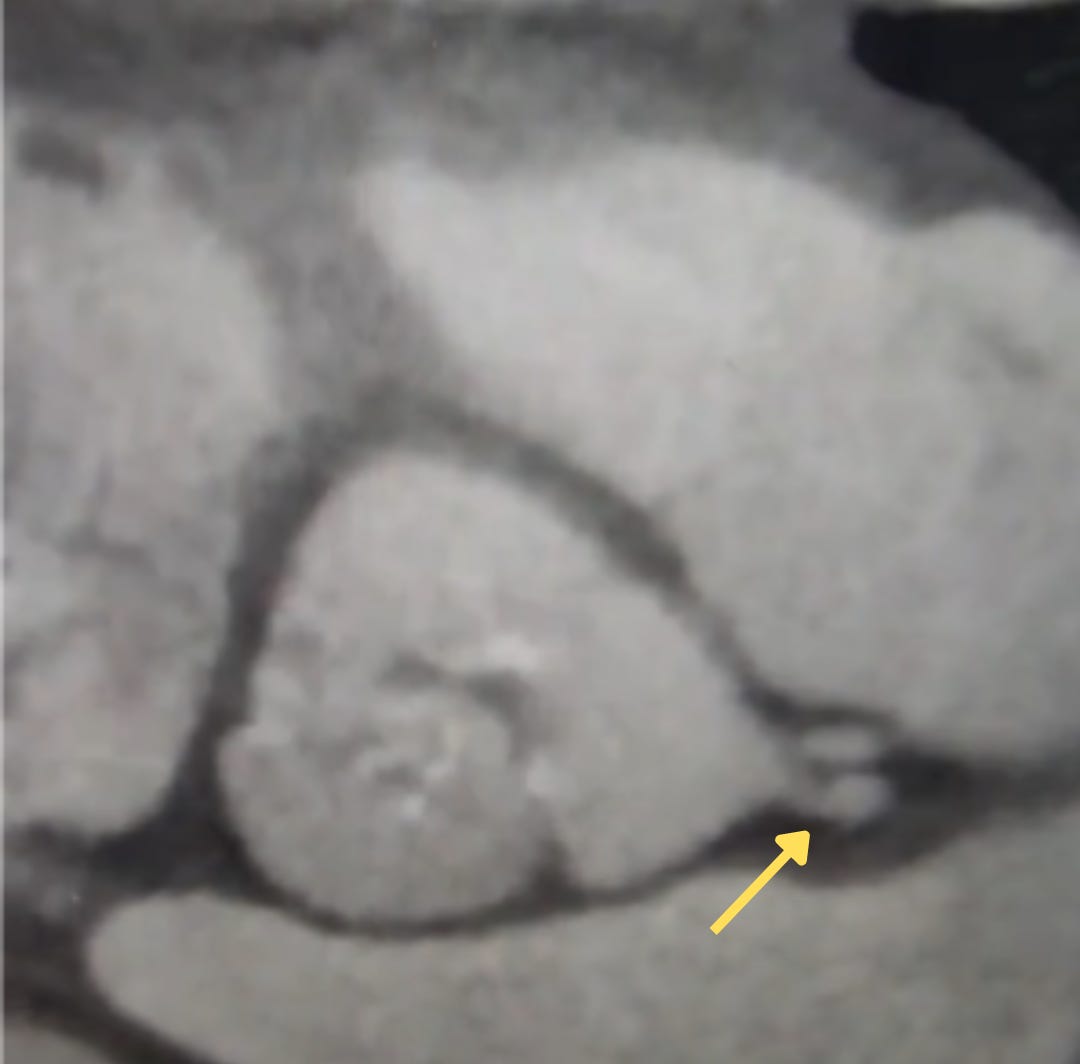

Antes da imagem da semana, vamos à resposta do desafio da semana passagem: ausência de TCE!

Note como a DA e a CX originam-se do seio esquerdo de óstios independentes (seta amarela) (seria essa uma evolução da nossa anatomia, anulando o risco de doença de TCE?)